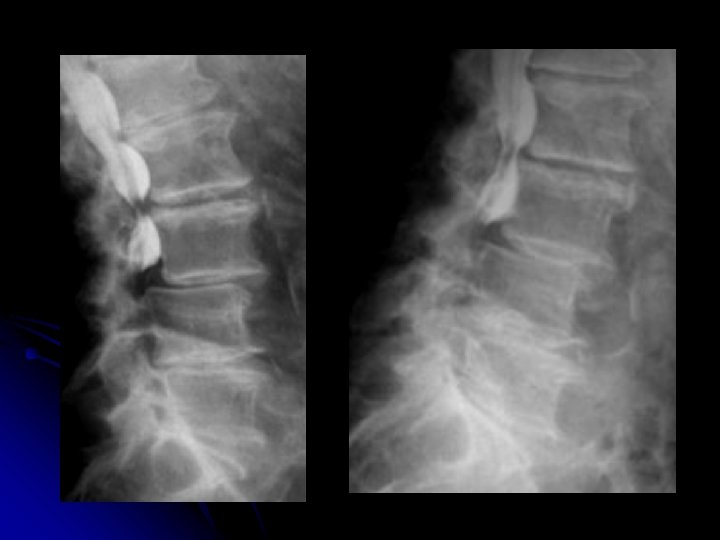

Rachis lombaire de profil

l Statique rachidienne l Morphologie et structure des corps vertébraux, l Hauteur des espaces inter-vertébraux l Morphologie des arcs postérieurs

Hémisacralisation de L 5